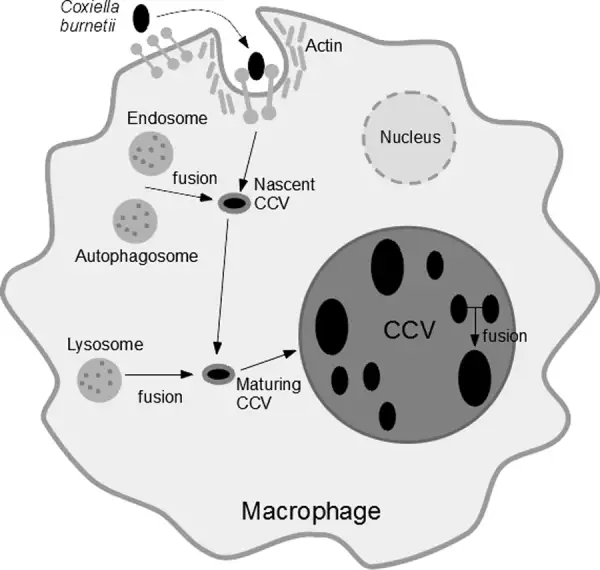

当伯内特考克斯氏体进入人体后,它的入侵策略堪称完美。它主要通过呼吸道进入,被肺泡巨噬细胞吞噬——这本应是免疫系统的第一道防线,但这种细菌却将吞噬作用变成了入侵的通道。细菌进入巨噬细胞后,被包裹在一个叫做吞噬体的膜结构中。正常情况下,吞噬体会与溶酶体融合,溶酶体内的酸性环境和消化酶会将入侵者彻底摧毁。但伯内特考克斯氏体进化出了一个惊人的对策:它不仅不逃避这种融合,反而主动促进它。它需要的正是溶酶体的酸性环境。

这种细菌携带的酸性磷酸酶可以中和吞噬体的杀伤性物质,同时它利用宿主细胞的营养在酸性的吞噬溶酶体中繁殖。这个特殊的结构被称为"考克斯氏体包含泡"(CCV)。在这个改造过的细胞器内,细菌开始疯狂复制。它们会产生一种特殊的Dot/Icm型IV型分泌系统,向宿主细胞注射数百种效应蛋白,操纵宿主细胞的信号通路,阻止细胞凋亡,确保自己的生存和繁殖。当细菌数量达到一定程度时,包含泡会膨胀到几乎充满整个宿主细胞,最终导致细胞破裂,释放出数百个新的细菌,每个都可以感染新的细胞。